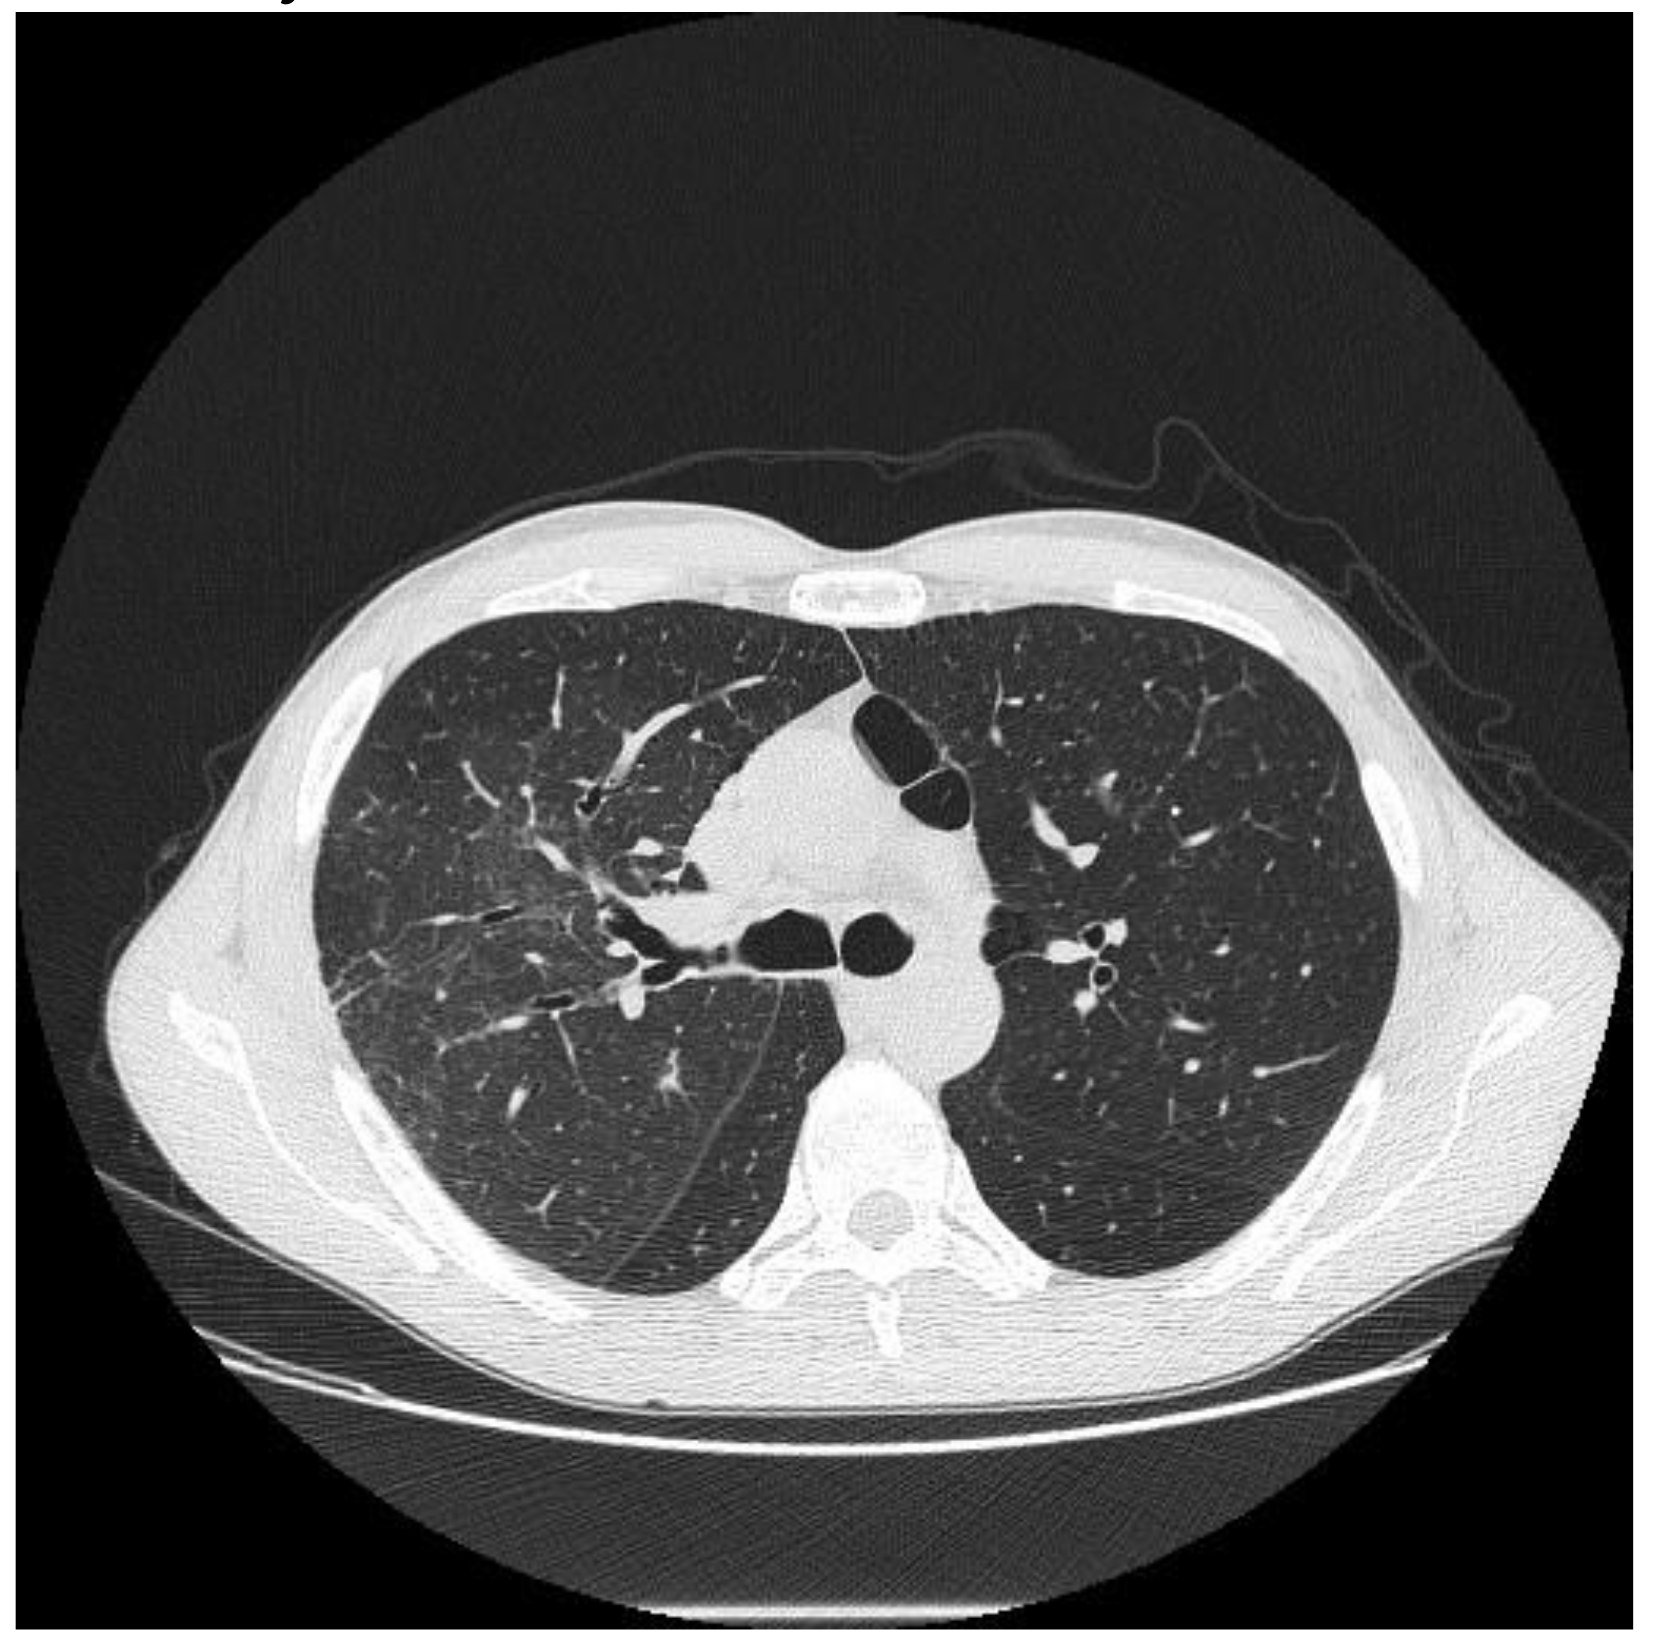

| HRCT Pattern | Associated Drugs |

|---|---|

| Fibrotic pattern | Nitrofurantoin (chronic toxicity), methotrexate, sulfalazina, rituximab, tocilizumab, bleomycin, busulfan, cyclophosphamide (chronic toxicity), amiodarone (form with fibrous course), tocainide, cocaine |

| Organizing pneumonia | Nitrofurantoin (chronic toxicity), methotrexate |

| Mosaic pattern | Nitrofurantoin (acute toxicity), methotrexate, sulfalazina |

| Isolated ground glass | Rituximab, tocilizumab, cyclophosphamide (acute reaction), amiodarone (initial stage), cocaine |

| Alveolar hemorrhage | Penicillamine, rituximab, cocaine |

| Pulmonary edema | Acetyl-salicylic acid, mitomycin |

| Pleural effusion | Sulfonamides, methotrexate |